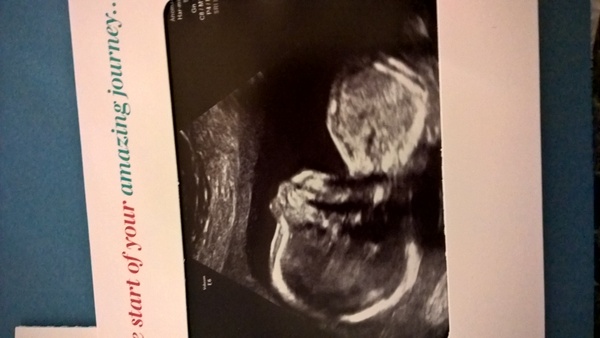

Loving all the lovely scan news.

.. My growth scan is on Monday. Can't wait.